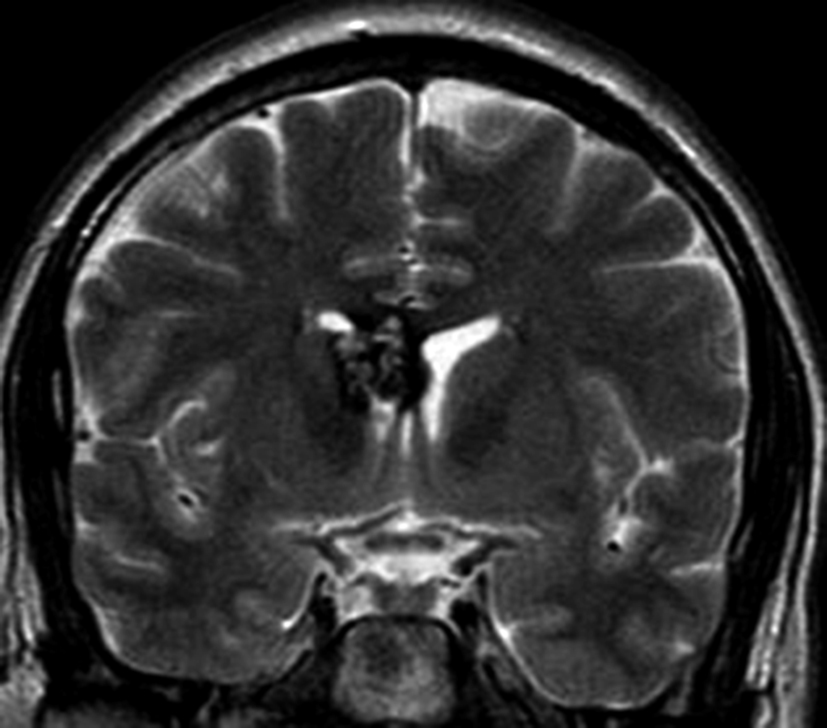

Con los hallazgos tomográficos, no se efectúan planteos diagnósticos y se realiza una resonancia magnética con la finalidad de obtener más datos semiológicos en busca de una aproximación diagnóstica. Se realizó el estudio por medio de secuencias T 1, FSE T 2, FLAIR, SWI y Difusión, en cortes axiales, FSE coronal y sagital T 1. Se realiza la administración de gadolinio DTPA en los tres planos. Se evidencia la lesión bien definida a nivel del ventrículo lateral derecho, que involucra al tronco del cuerpo calloso (Figura 2- C y 3- B). Presenta intensidad de señal heterogénea en secuencias T1 y T2 (Figura 3 y Figura 4). En secuencia ecogradiente se observa una señal marcadamente hipointensa y heterogénea, con un halo hipointenso bien definido (Figura 2- C). No presenta realce significativo tras la administración de Gadolinio (Figura 2- B) y en la secuencia de difusión no presenta restricción.

Figura 4

a y b) Imágenes coronales T2, Ay B. se evidencia la lesión con epicentro en el asta frontal del ventrículo lateral derecho y la extensión al cuero calloso.